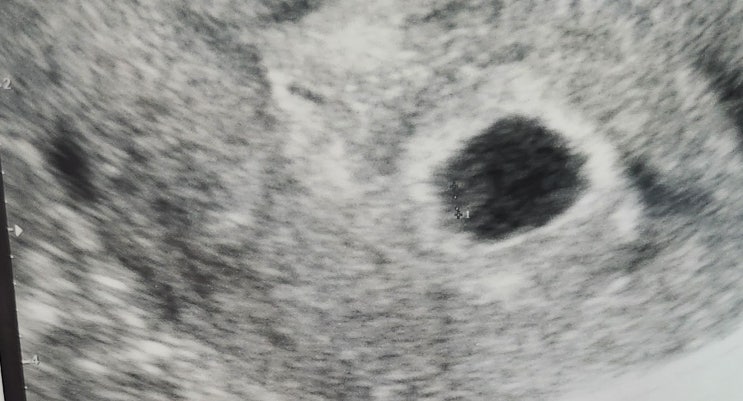

[임신 5주차의 기록] 아기집의 확인

안녕하세요 이웃님들~~ 임신 5주차에 ㅎㅎ 아기집과 난황을 작게나마 확인하고 왔답니다 ㅎㅎ~ 근데 첫번째...